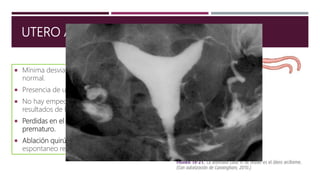

UTERO ARQUEADO

 Mínima desviación del desarrollo uterino

normal.

 Presencia de un tabique en la línea media.

 No hay empeoramiento notable en los

resultados de la esfera reproductiva.

 Perdidas en el segundo trimestre y parto

prematuro.

 Ablación quirúrgica únicamente en aborto

espontaneo repetitivo.